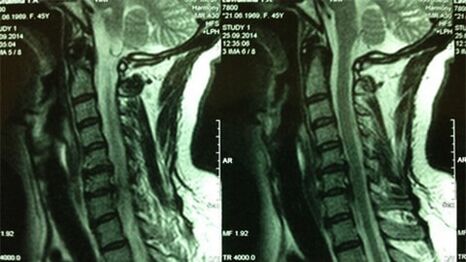

- X -raio do departamento cervical; No estágio inicial do processo, a ressonância magnética do departamento cervical será mais informativa - garantirá a visualização de alta qualidade de tecidos sólidos e moles - mostrará a condição dos discos intervertebrais, a presença de osteófitos, deformações, danos às raízes nervosas e vasos sanguíneos; avaliará a condição dos ligamentos, músculos, tecido ósseo;